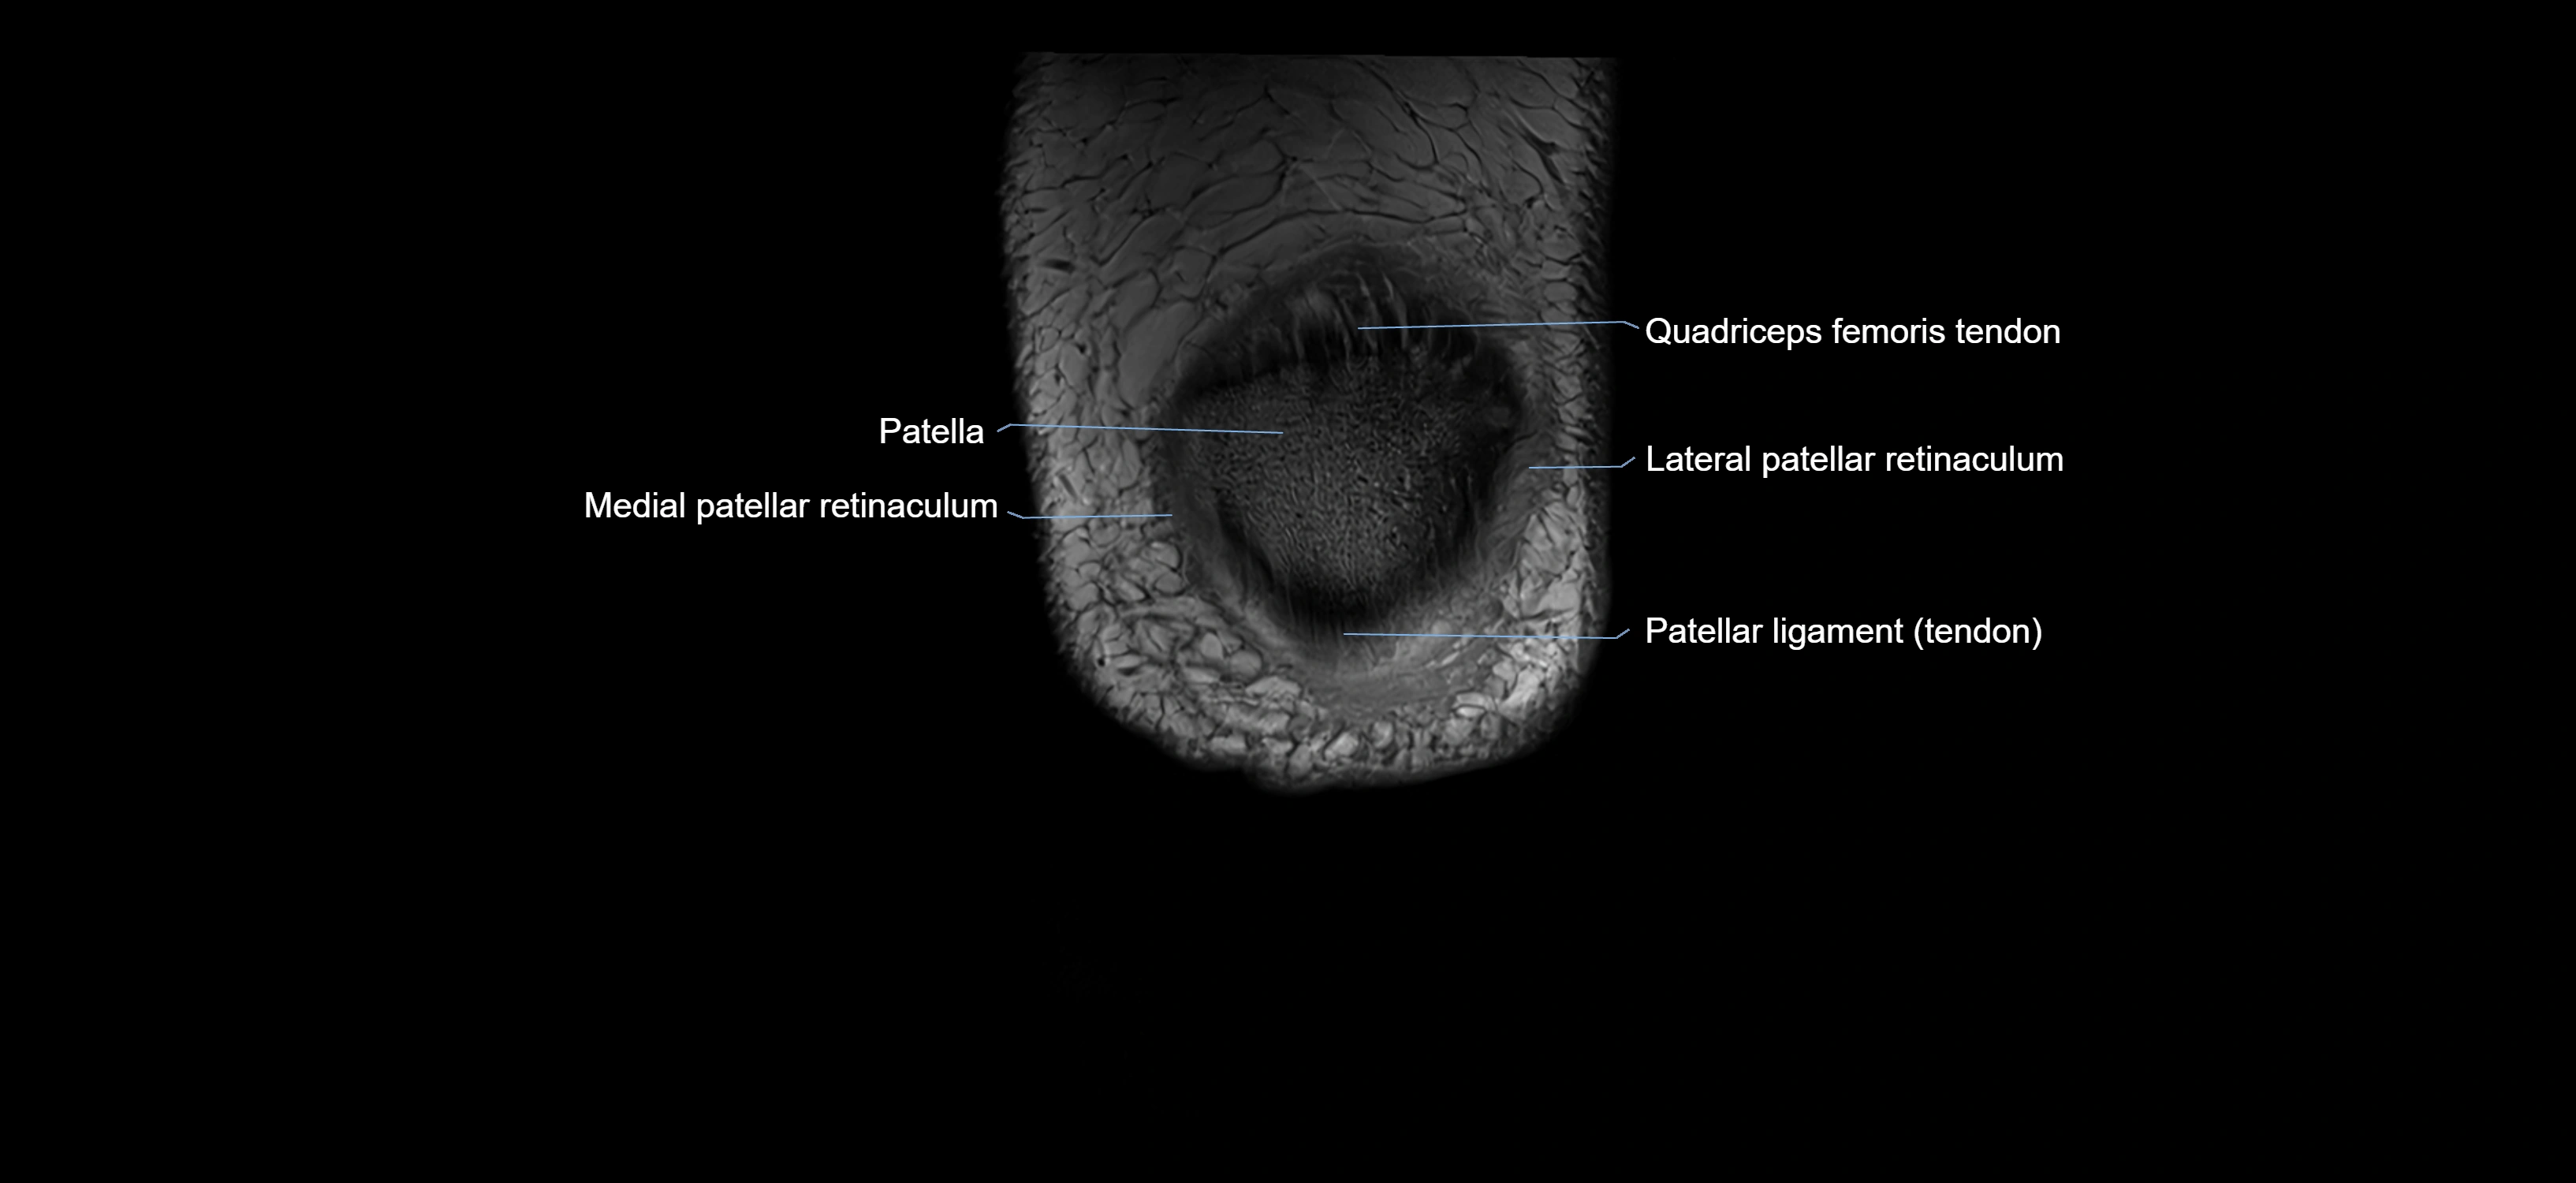

- Patella

- Lateral patellar retinaculum

- Medial patellar retinaculum

- Patellar tendon (patellar ligament)

- Distal quadriceps femoris tendon